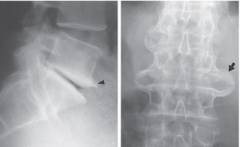

Рентгенография — ключевой метод диагностики остеофитов благодаря доступности и неинвазивности. На начальном этапе остеофиты выглядят как небольшие заостренные образования на передней верхней или нижней части тел позвонков, обычно не превышающие несколько миллиметров. Со временем они могут увеличиваться. Значительные остеофиты в области позвоночника на рентгеновских снимках напоминают птичьи клювы. Важно установить местоположение и форму остеофитов, а также проанализировать их структуру, контуры и размеры. Рентгенография также может выявить другие патологические изменения в позвоночнике.

Рентгенография — основной метод диагностики остеофитов благодаря доступности и неинвазивности. На начальном этапе остеофиты выглядят как небольшие заострения на передней поверхности тел позвонков. Со временем они могут увеличиваться и принимать форму птичьих клювов. Важно определить не только локализацию и форму остеофитов, но и их структуру и размеры.